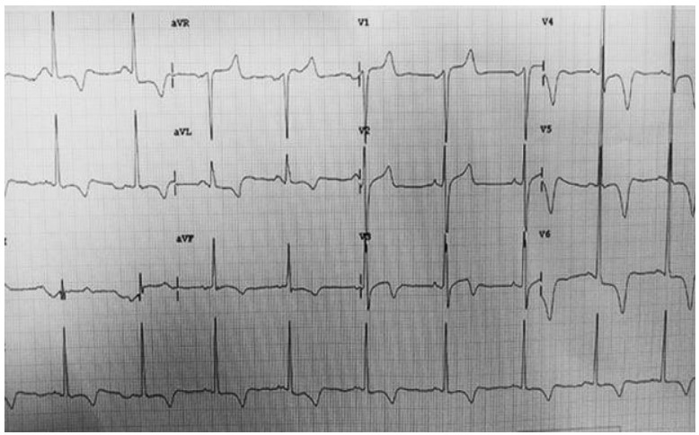

Paciente, sexo masculino, 65 anos, hipertenso, diabético e dislipidêmico. Chega na emergência, com quadro clínico de precordialgia em aperto, com irradiação para mento, há 4 horas. Heart score 5. Eletrocardiograma de admissão com ritmo sinusal, alteração difusa e inespecífica de repolarização ventricular. Troponina convencional positiva. De repente, paciente com pulso, começou a apresentar o seguinte traçado do monitor.

Segundo as Diretrizes da Sociedade Brasileira de Cardiologia sobre Angina Instável e Infarto Agudo do Miocárdio sem Supradesnível do Segmento ST – 2021. Assinale a alternativa correta.